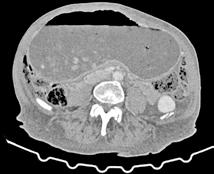

A las 36 horas de vida presenta nuevo empeoramiento respiratorio, se solicita estudio completo y se realiza punción lumbar (a pesar de paráme tros infecciosos negativos en la analítica). Se obtiene líquido purulento y se procede a escalada de tratamiento a ceftriaxona y ampicilina (mantiene tratamiento durante 7 y 3 días respectivamente, no aislándose microorga nismos en muestras de líquido cefalorraquídeo ni hemocultivos). Se repite la radiografía de tórax en la que se evidencia neumotórax de nueva apa rición e imagen sugestiva de neumomediastino. Ante estos hallazgos, se solicita TC de tórax que confirma el diagnóstico y descarta la existencia de causas desencadenantes (Figura 2). Se mantienen requerimientos de VMNI durante 4 días más, siendo finalmente posible la desescalada gradual a oxigenoterapia con gafas nasales durante 4 días. Se consigue retirada del soporte respiratorio de manera completa pasados 8 días, realizando un control con TC de tórax a los 9 días de vida (Figura 3) que muestra mejoría significativa acompañándose de una recuperación clínica completa.

Figura 2. (Izq.) radiografía de tórax en proyección AP a las 36 horas de vida donde se objetiva neumotórax de nueva aparición (flechas azules) y una zona de hiperclaridad alrededor de la silueta cardíaca que sugiere importante neumomediastino (estrellas amarillas). (Der.) TC de tórax sin contraste intravenoso en ventana de pulmón que confirma la presencia de neumomediastino (estrella amarilla). Se objetivan focos de consolidación periféricos y bandas lineales de densidad aire paralelas y adyacentes a las vainas broncovasculares (flechas amarillas).

Figura 3. TC de tórax sin contraste intravenoso en ventana de pulmón a los 9 días de vida sin alteraciones en el parénquima y neumomediastino prácticamente resuelto.